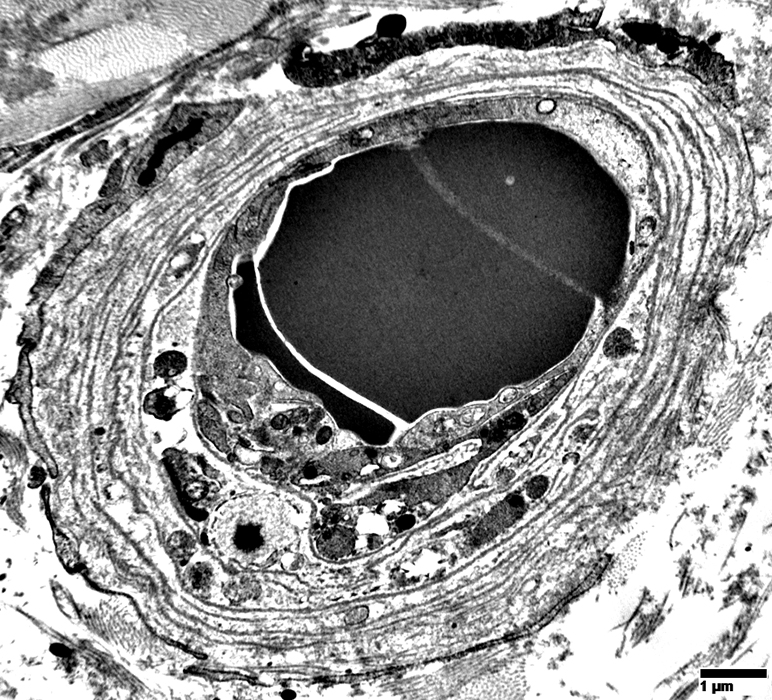

Endomysial Capillaries: Basal Lamina

Irregular increase in basal lamina layers around capillaries (Arrows)

Endomysial Capillary Walls: Multiple circumferential layers of Basal Lamina

Endomysial Capillary Basal Lamina: Multiple circumferential layers